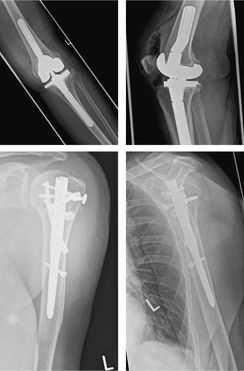

Eine 86-jährige, selbstversorgende Frau, wird auf der Straße von einem abbiegenden PKW bei geringer Geschwindigkeit angefahren und stürzt. Entsprechend den neuen S3-Leitlinie Polytrauma/Schwerverletzten-Behandlung wird eine niedrigschwellige Indikation zur Schockraumbehandlung und CT-Diagnostik (Polytrauma-CT) angelegt, wodurch sich eine valgisch impaktierte Humeruskopf-3-Segment-Fraktur links und eine Tibiakopffraktur Schatzker V links zeigten (Abbildung 5). Anamnestisch berichtet die Patientin über vorbestehende belastungsabhängige Schmerzen im Bereich des linken Knies im Sinne einer Arthrose. Aufgrund der zu erwartenden Unfähigkeit, bei der postoperativen Mobilisation eine Teilbelastung des linken Beines einhalten zu können, wurde von einer Osteosynthese der Tibiakopffraktur abgesehen und der Implantation einer teilgekoppelten, stemgeführten Knieprothese der Vorzug gegeben [11, 12] (Abbildung 6). Auch wenn sich die Humeruskopffraktur von der Morphologie her für eine konservative Therapie geeignet hätte, wurde in diesem Fall zugunsten einer frühfunktionellen Nachbehandlung und besseren Mobilisierung eine Nagelosteosynthese durchgeführt (Abbildung 6). Nach erfolgter frührehabilitativer Komplexbehandlung konnte die Patientin selbstständig auf Stationsebene mobil in die Anschlussheilbehandlung entlassen werden.

Abbildung 6: Postoperative Röntgenkontrollen a.p. und seitlich nach Versorgung der Tibiakopffraktur mit teilgekoppelter,

stemgeführter Knieprothese mit lateralem Augment und der Humeruskopffraktur mit Nagelosteosynthese.